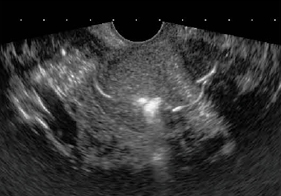

子宮腔内の描写は,バルーンの付いているチューブよりも,バルーンなしのチューブが使いやすい(アトム栄養カテーテル,4Fr:アトムメディカル社製)。造影は,単純な生理食塩水による陰性造影の方が明瞭な画像が得られる(図11)。

![]() 図11 生理食塩水による陰性造影 不妊で管理中,子宮内にポリープが見つかり,着床不全の原因になりうると推測。 ポリープ切除術,子宮内膜掻爬の後,妊娠した。 |